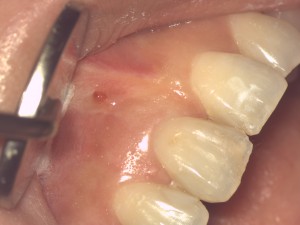

根の先の歯肉にオデキのようなものが出来た

「前歯の根の先におできのようなものが出来ているので見て欲しい」

この病状は根尖性歯周炎と言います。

膿が溜まると膿はそこから出ようという力が働きます。そうすると、組織の弱い部分を通じて歯肉を突き破り、膿の路が出来ます。

これがおできの正体です。

排膿路であるこの路を昔は「フィステル」と呼んでいました。しかし、フィステルの定義は内臓間の異常交通路や上皮に覆われた通路となっているため、AAE(米国歯内療法学会)では2003年から「sinus tract」に統一した。

このような状態になった理由は、こちらの患者さんでは1年前にコンポジットレジンの白い詰め物が適切に治療されていなかったことが考えられます。

コンポジットレジンの接着技法のどこか不備があり、そのために接着が阻害され歯とコンポジットレジンの間にスキマが出来て、そこから細菌感染して根の先に病巣、膿を作ったもの考えられます。

昨日は根管治療を行い歯の中を洗浄・消毒しました。

経過が良ければ、このSinus Tract は間もなく消えるでしょう。